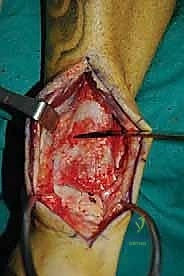

الغوص العميق في جراحة الطعم الخيفي الهيكلي (Structural Allograft Reconstruction)

يهدف هذا الإجراء العبقري إلى استبدال الغضروف والعظم التالفين والميتين بنسيج سليم تماماً مأخوذ من متبرع متوفى (طعم خيفي - Allograft). هذا الطعم يتم تعقيمه وحفظه في بنوك الأنسجة العالمية وفقاً لأعلى المعايير الطبية الصارمة لضمان خلوه من أي أمراض معدية والحفاظ على حيوية الخلايا الغضروفية.

- الترميم التشريحي الحقيقي: يسمح باستعادة الشكل الهندسي الدقيق لعظم الكاحل، بما في ذلك المنحنيات المعقدة لكتف التالوس.